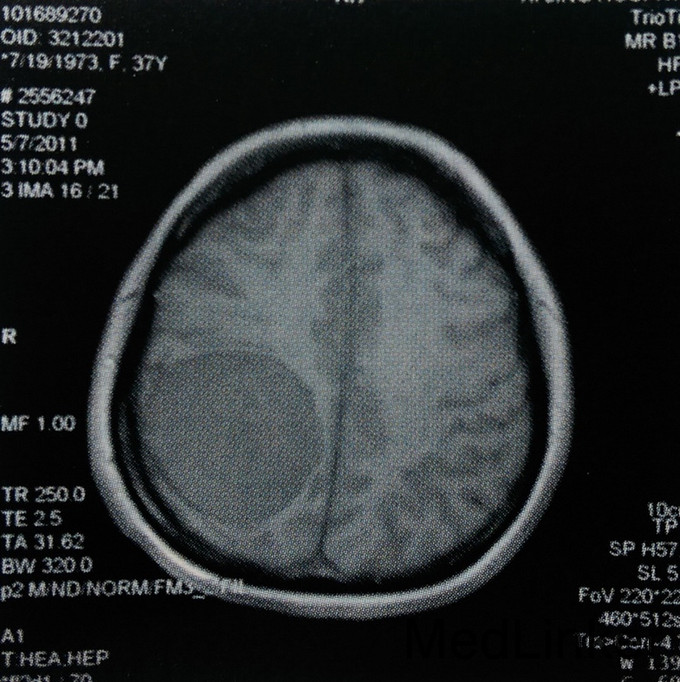

患者,女,37岁。主因左上肢麻木2年入院。 患者2年前无诱因出现左侧肢体麻木,无乏力、活动受限,未就诊。此后上述症状进行性加重,遂在当地医院以颈椎病对症治疗,未好转。行头颅MRI检查:右侧颞顶枕部见类圆形占位,大小约5.8cmх5.2cmх5.4cm,T1WI呈稍低信号,T2WI呈稍高信号,边缘尚清楚,压迫右侧脑室后角。Gd-DTPA增强后,明显强化,合并宽基底与脑膜相接,可见鼠尾征。门诊以“右顶叶巨大肿瘤”收入我科。无相关既往史、个人史及家族史。